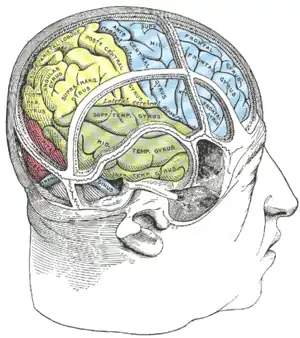

| Hemispatial neglect is most frequently associated with a lesion of the right parietal lobe (in yellow, at top). | |

Hemispatial neglect is a neuropsychological condition in which, after damage to one hemisphere of the brain (e.g. after a stroke), a deficit in attention and awareness towards the side of space opposite brain damage (contralesional space) is observed. It is defined by the inability of a person to process and perceive stimuli towards the contralesional side of the body or environment.[1] Hemispatial neglect is very commonly contralateral to the damaged hemisphere, but instances of ipsilesional neglect (on the same side as the lesion) have been reported.[3]

Hemispatial neglect results most commonly from strokes and brain unilateral injury to the right cerebral hemisphere, with rates in the critical stage of up to 80% causing visual neglect of the left-hand side of space. Neglect is often produced by massive strokes in the middle cerebral artery region and is variegated, so that most sufferers do not exhibit all of the syndrome's traits.[4] Right-sided spatial neglect is rare because there is redundant processing of the right space by both the left and right cerebral hemispheres, whereas in most left-dominant brains the left space is only processed by the right cerebral hemisphere. Although it most strikingly affects visual perception ('visual neglect'), neglect in other forms of perception can also be found, either alone or in combination with visual neglect.[5]

For example, a stroke affecting the right parietal lobe of the brain can lead to neglect for the left side of the visual field, causing a patient with neglect to behave as if the left side of sensory space is nonexistent (although they can still turn left). In an extreme case, a patient with neglect might fail to eat the food on the left half of their plate, even though they complain of being hungry. If someone with neglect is asked to draw a clock, their drawing might show only the numbers 12 to 6, or all 12 numbers might be on one half of the clock face with the other half distorted or blank. Neglect patients may also ignore the contralesional side of their body; for instance, they might only shave, or apply make-up to, the non-neglected side. These patients may frequently collide with objects or structures such as door frames on the side being neglected.[1]

Brain areas in the parietal and frontal lobes are associated with the deployment of attention (internally, or through eye movements, head turns or limb reaches) into contralateral space. Neglect is most closely related to damage to the temporo-parietal junction and posterior parietal cortex.[7] The lack of attention to the left side of space can manifest in the visual, auditory, proprioceptive, and olfactory domains. Although hemispatial neglect often manifests as a sensory deficit (and is frequently co-morbid with sensory deficit), it is essentially a failure to pay sufficient attention to sensory input.

Although hemispatial neglect has been identified following left hemisphere damage (resulting in the neglect of the right side of space), it is most common after damage to the right hemisphere.[8] This disparity is thought to reflect the fact that the right hemisphere of the brain is specialized for spatial perception and memory, whereas the left hemisphere is specialized for language - there is redundant processing of the right visual fields by both hemispheres. Hence the right hemisphere is able to compensate for the loss of left hemisphere function, but not vice versa.[9] Neglect is not to be confused with hemianopsia. Hemianopsia arises from damage to the primary visual pathways cutting off the input to the cerebral hemispheres from the retinas. Neglect is damage to the processing areas. The cerebral hemispheres receive the input, but there is an error in the processing that is not well understood.